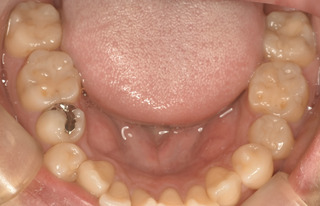

治療前

(画面左の金属)